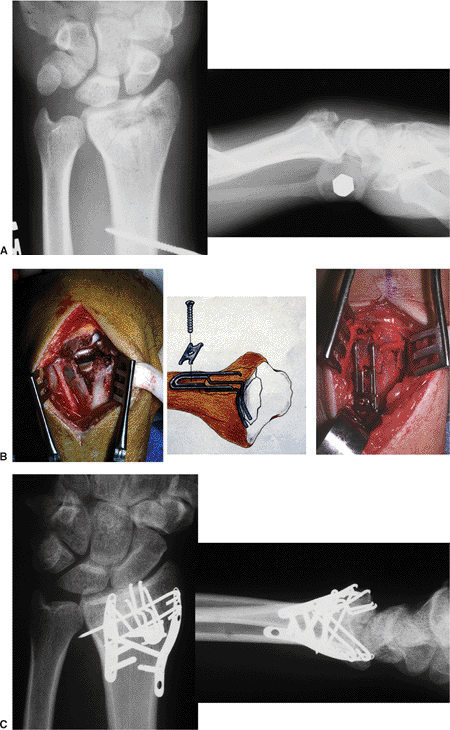

|

Figure 13.19. A complex intra-articular fracture treated with fragment specific fixation using wire forms and pin plate. A. The x-rays of the fracture. B. The use of the wire form to support the impacted articular fracture. C. X-rays of the healed fracture. (Case courtesy of Dr. Robert Medoff).